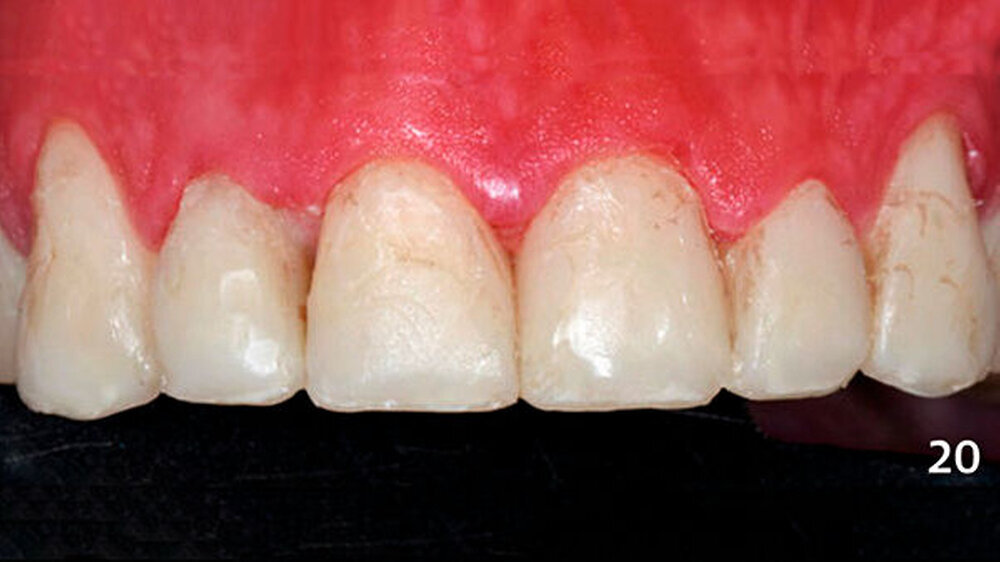

Die schwer zugänglichen Approximalflächen und -übergänge wurden mit oszillierenden, einseitig diamantierten Feilen (Proxo Shape Flexible, Fa. Intensiv, Grancia, Schweiz) ausgearbeitet und geglättet (Abb. 10). Mit dieser Technik wurden die Seitenzähne im Unterkiefer schrittweise aufgebaut und am Ende poliert (Abb. 11). Abschließend erfolgte die Versorgung der Frontzähne im Unterkiefer mit Komposit unter Verwendung der Bodymasse (Farbe A3B) des oben genannten Komposits (Abb. 12, 13).

Nach der Bisshebung im Unterkiefer wurden die erosiven Frontzahndefekte im Oberkiefer ebenfalls mit Kompositadhäsiv versorgt (Abb. 14). Zunächst wurden die bukkalen Zahnhartsubstanzverluste freihändig mit Komposit aufgebaut (Abb. 15), und es wurde eine Alginatabformung genommen. Im zahntechnischen Labor wurden die inzisalen Anteile der Zähne aufgewachst, sodass anschließend ein Silikonschlüssel angefertigt werden konnte (Abb. 16).

Die Dentinmassen wurden dann von bukkal im inzisalen Anteil mit einer dünnen Schicht Schmelzmasse überschichtet, die im zervikalen Bereich der Zähne mit Bodymasse (Farbe A3B) ergänzt wurde und an diesem Tage aufgrund Zeitmangels nur grob ausgearbeitet wurden. Die Restaurationen stellten sich in der darauffolgenden Sitzung mit oberflächlichen Verfärbungen dar (Abb. 20) und wurden nun vollständig ausgearbeitet und poliert (Abb. 21).